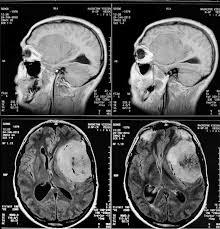

Наиболее информативным видом диагностики менингиом является Магнитно-резонанасная томография (МРТ). При помощи МРТ можно определить точное расположение менингиомы (в височной , лобной доле и т. д.), кровоснабжение, состояние сосудов, особенности строения. Компьютерная томография (КТ) используется также часто, но на менее информативна. На КТ неплохо визуализируются вкрапления кальция, состояние костей черепа.